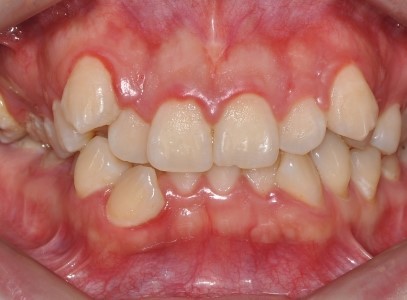

분당 판교 교정치과|10대 여학생 심한 덧니·중심선 편위, 선천적 결손치 발치교정 치료 사례